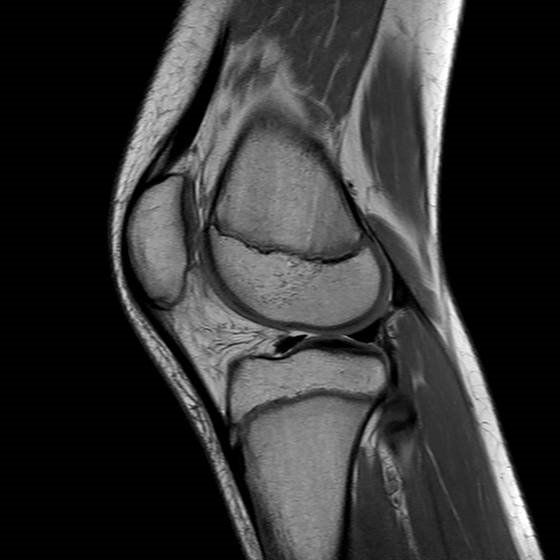

La Risonanza Magnetica a basso campo magnetico (0.32 T) in uso presso ARS RADIOLOGICA srl (RM MRJ 3300, Paramed) è una macchina dedicata allo studio delle articolazioni (ginocchio, caviglia, piede, gomito, polso, mano, spalla ed anca).  Inoltre permette di studiare il rachide cervicale e lombare.

Con questo apparecchio RM si ottengono immagini di buona qualità diagnostica, con il vantaggio per il paziente di introdurre nel magnete il solo arto da studiare, evitando la sgradevole sensazione di costrizione in un ambiente chiuso.